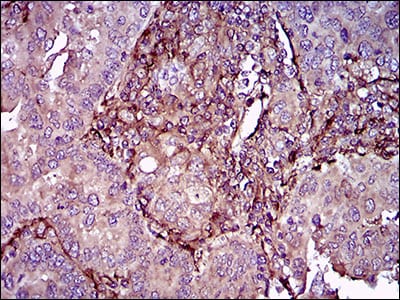

Immunohistochemical analysis of paraffin-embedded human endometrial cancer tissues using AVP mouse mAb with DAB staining

Immunohistochemical analysis of paraffin-embedded human cerebellum tissues using AVP mouse mAb with DAB staining

Immunohistochemical analysis of paraffin-embedded Rat spleen using AVP mouse mAb with DAB staining

Immunohistochemical analysis of paraffin-embedded Rat kidney using AVP mouse mAb with DAB staining